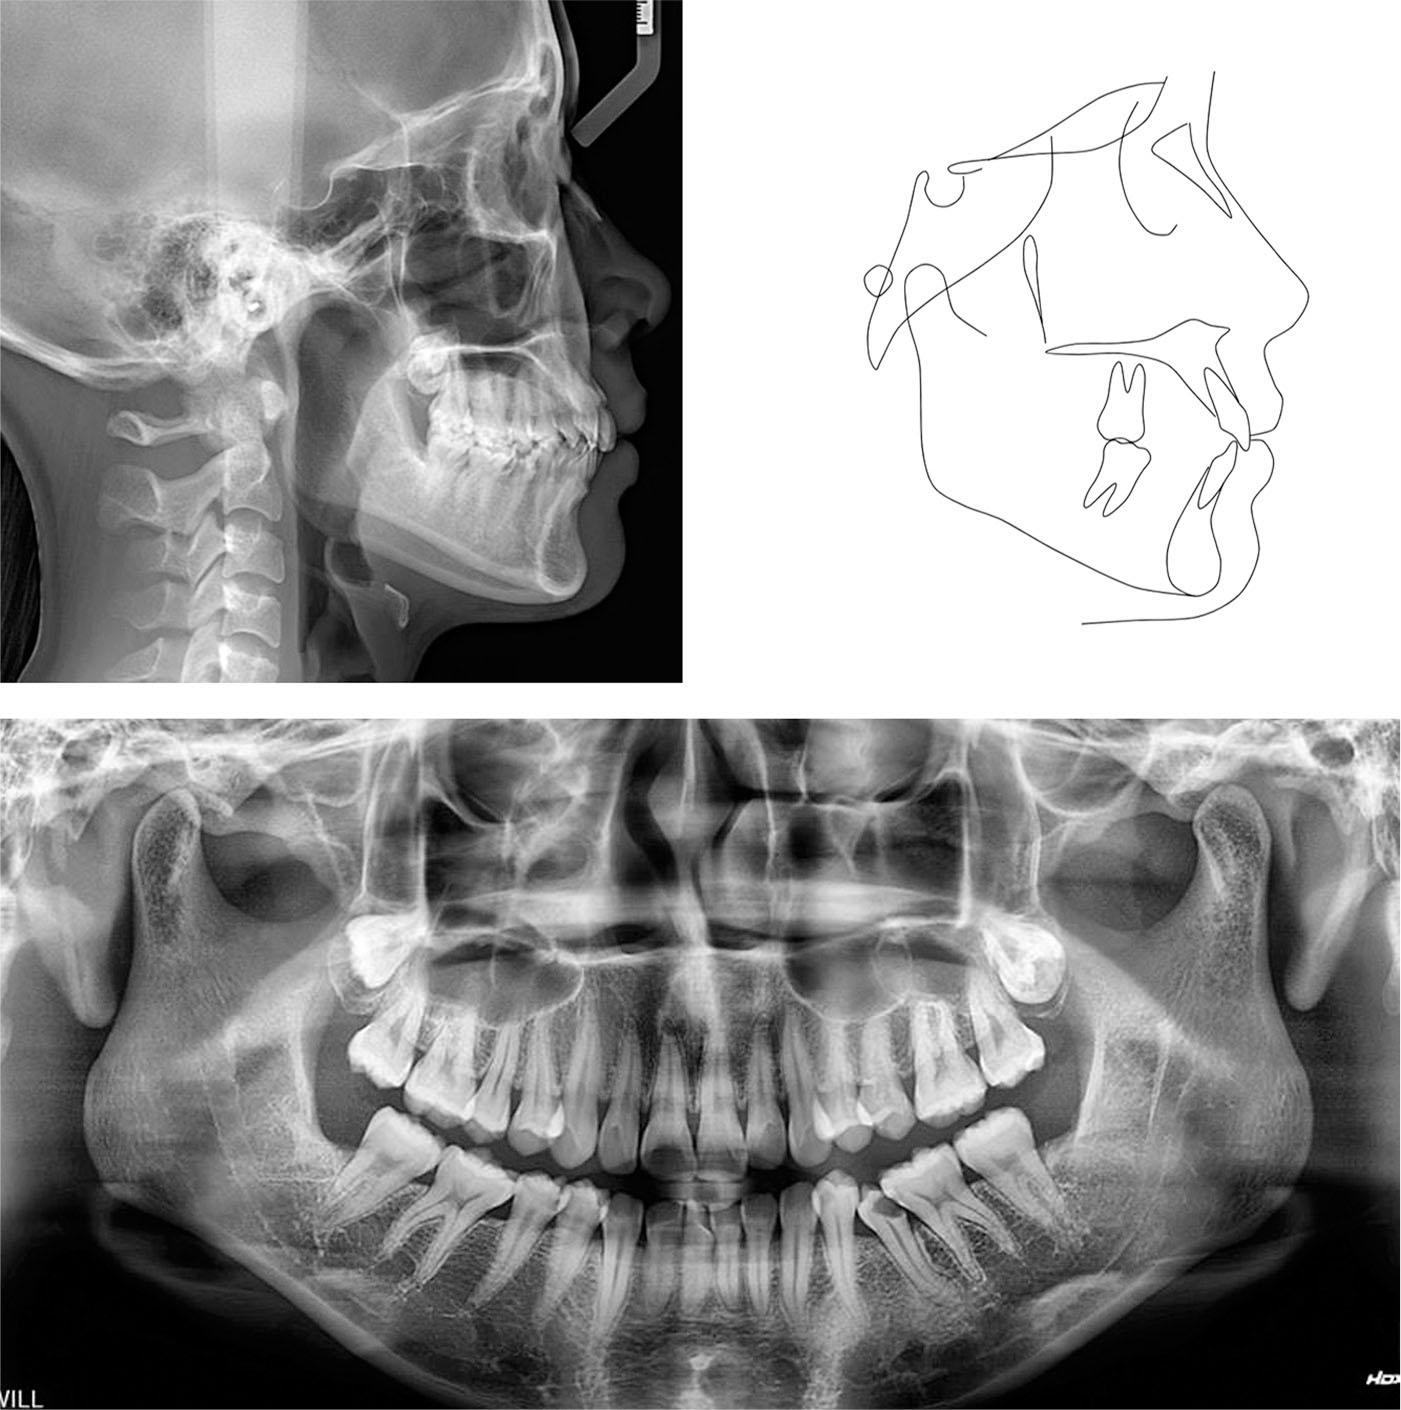

The lateral cephalometric analysis revealed a skeletal Class I relationship with a normally positioned maxilla and mandible (SNA, 81.8°; SNB, 78.2°; ANB, 3.6°). The lower anterior facial height was within the normal range (FMA, 27.4°). The upper incisors were normally inclined (U1-SN,101.7°) while the lower incisors were slightly proclined (L1-MP, 96.8°). The soft tissue findings showed that the upper and lower lips were normally placed (upper lip to E-line, -1.2 mm; lower lip to E-line, -0.7 mm) (Table I). The panoramic radiograph showed the presence of all teeth except the mandibular third molars and confirmed the mesial inclination of the mandibular molars and second premolars (Figure 3).

Pretreatment radiographs and tracing.